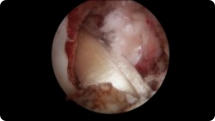

Arthroscopic image of a rotator cuff tear Arthroscopic image of a repaired rotator cuff

Rotator Cuff Tear

Rotator Cuff Repair